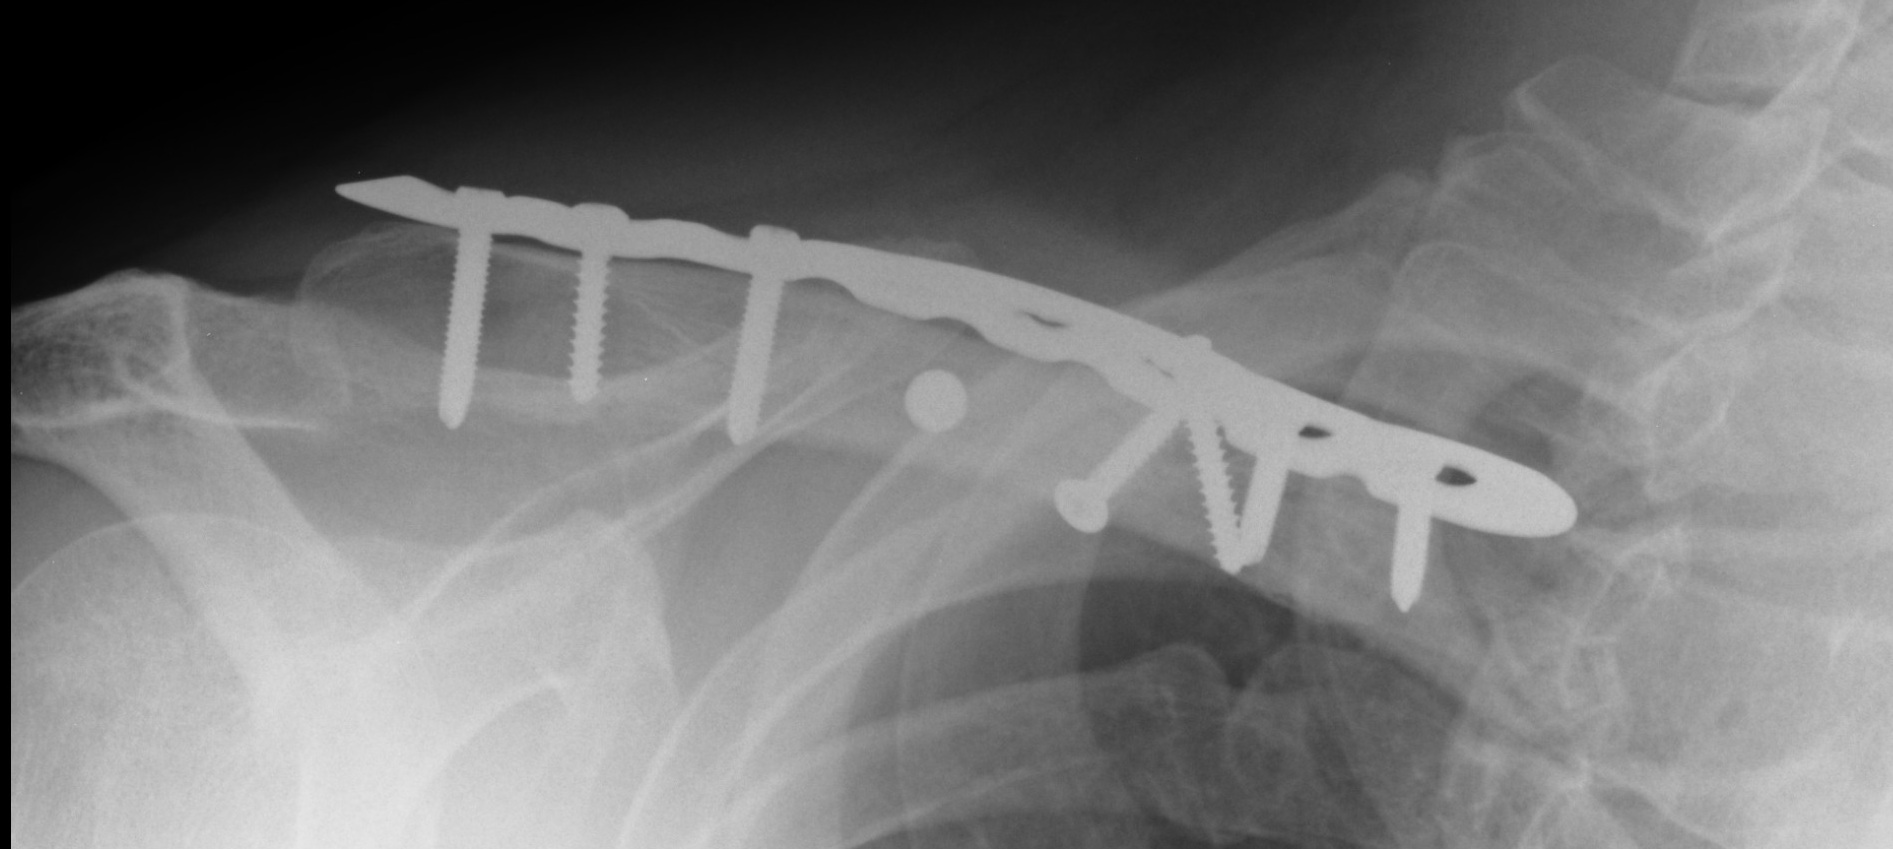

A multi-fragmentary fracture of the clavicle fixed with a plate and screws